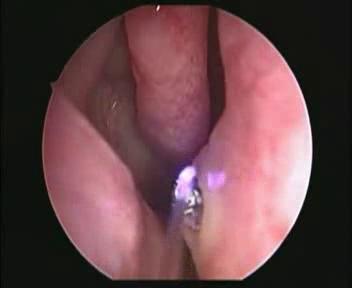

Zabieg ten wykonywany

laserem CO2 lub diodowym jest

zdecydowanie krótszy niż tradycyjny, prawie bezkrwawy i najczęściej nie

wymaga też zakładania opatrunków do nosa po jego wykonaniu (w tym tzw.

tamponady). Nie używa się w nim też klasycznych narzędzi chirurgicznych

- z reguły nie jest potrzebne nawet znieczulenie w formie zastrzyku

podawanego do nosa jak ma to miejsce w "zwykłej" operacji. Zabieg

pozwala zlikwidować główne przewężenia w obrębie nosa, czyli poszerzyć

te miejsca, które najbardziej utrudniają oddychanie.